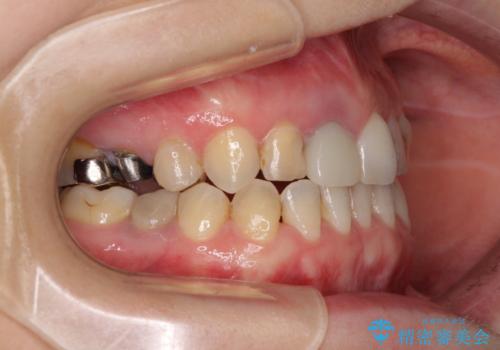

前歯のクロスバイトはインビザラインで改善し、抜歯が必要な部分はインプラントを、その他むし歯が進行している歯はセラミッククラウンによる補綴治療することとしました。

仕事がお忙しく、インビザラインをあまりしっかりと使用できなかったようで、何とか長い期間をかけて歯列を整えることができました。